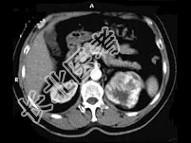

- 多项选择题男,65岁, 左侧腰背部胀痛伴无痛性全程血尿3个月余,CT平扫及增强检查如图所示, 下列说法正确的是 ( )

A、平扫时见左肾上极有一软组织肿块影,其边界较清楚

B、增强扫描肾皮质期可见肿块明显强化,其内亦有无强化区

C、增强扫描肾实质期可见肿块强化迅速下降,但密度比平扫时仍要高

D、考虑为左侧肾癌

E、考虑为左侧肾错构瘤